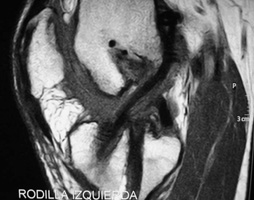

En todos los pacientes de ésta muestra fueron evaluadas radiografías y RMI para determinar las causas de la falla, dividiéndo a los pacientes en 2 grupos en virtud de si las cirugía primaria había sido efectuada por nuestro grupo de trabajo ó por otro. La causa más frecuente de fracaso en nuestra muestra fue el error técnico (75,8%), correspondiendo sólo el 46,8% a un túnel femoral anterior y el 28,5% a un túnel tibial posterior. (Figs.1, 2 y 3)

Figura 1: RX Cross pin protuyendo en artic. Patelofemoral. |

Figura 2: RMI Corte sagital. Combinación de túneles femoral y tibial anteriores. |